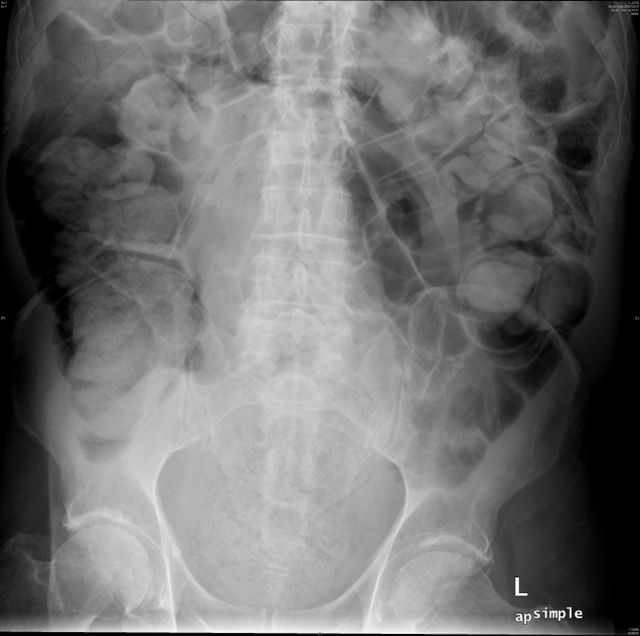

Diverticulosis de colon.

Diverticulosis de colon. Megacolon.

Dolico-megacolon.

Dilatación colónica. Diverticulosis.